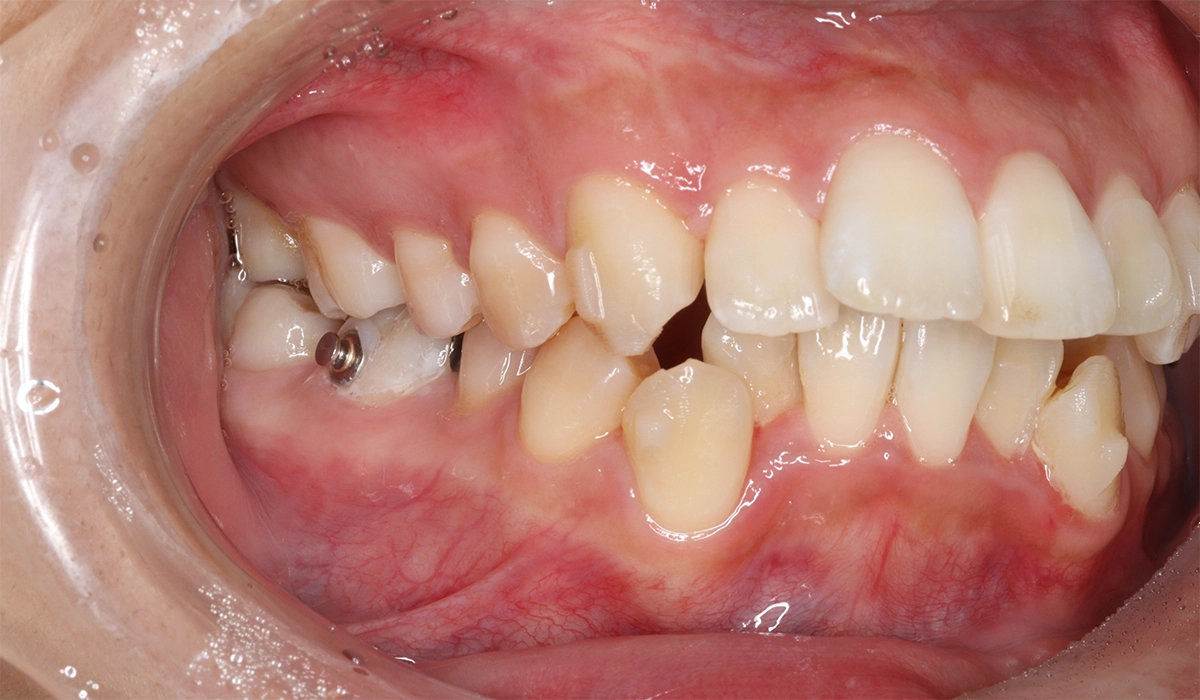

術前:右側

術後:右側